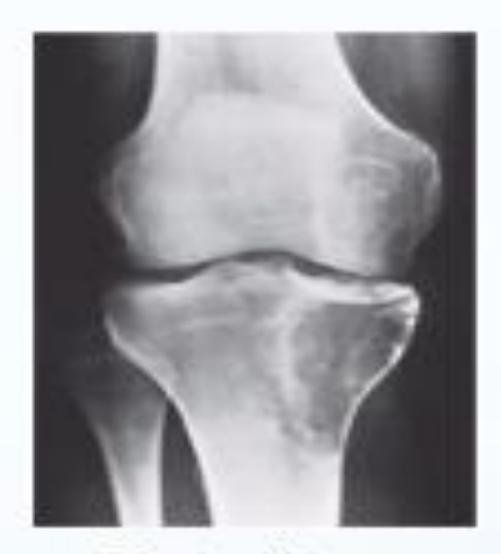

Q9: A 45-year-old male complained of left knee pain for 3 years that didnโt improve with conservative treatment. His x-ray is shown in Figure A. He underwent the procedure, as seen in Figure B. What is the aim of this procedure?

- B. Redistribute the patientโs weight.

Describe the findings:

- Joint space narrowing

- Subchondral sclerosis

- Osteophytes formation

Diagnosis: Osteoarthritis

A 60-year-old overweight lady presented to clinic with chronic pain in both knees. A standing AP x-ray of both knees is shown.

Q1: Mention TWO findings on this X-ray

- Narrowing of the joint space

- Osteophytes

Q2: What is the diagnosis?

- Bilateral knee osteoarthritis

AP & Lateral x-ray of the knee joint showing narrowing of joint space & sclerosis

Diagnosis?

- Knee Osteoarthritis

Management?

- Exercise & analgesics

- Intra-articular injection

- Knee arthroplasty (depends on the case)